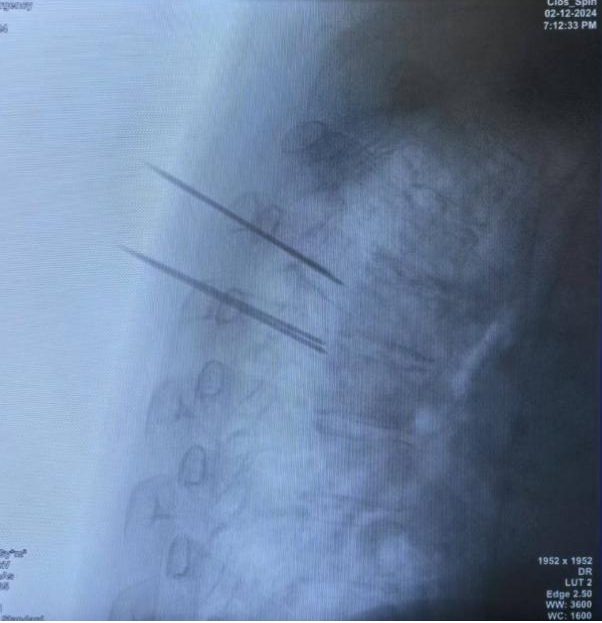

近日,我院骨病骨肿瘤外科胡勇教授团队利用手术机器人辅助,完成上胸椎转移性肿瘤的微创杂交手术。

患者,女,53岁,甲状腺癌术后2年,胸4、5及腰2椎体多发骨转移,胸背部无法药物控制的疼痛,即将病理性骨折。胡勇教授团队将MRI、3D-CT及PET-CT图像融合数据输入手术机器人进行精准规划设计,同步完成了3椎体的微创杂交手术,手术历时55分钟,术后无神经损伤并发症发生,患者疼痛消除,术后第二天即可下地行走。